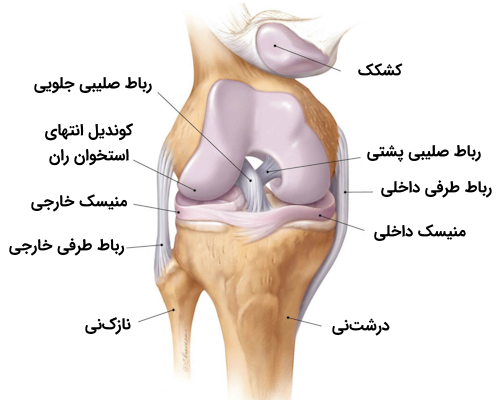

رباطهای صلیبی

رباطهای صلیبی زانو در حقیقت دو رباطی هستند که به صورت اُریب از یکدیگر عبور میکنند و به همین دلیل به صورت یک صلیب یا حرف «X» انگلیسی، در درون مفصل به نظر میآیند. با وجود آن که تقاطع این دو رباط در درون کپسول مفصلی است، آنها وارد حفره سینوویال نمیشوند و در خارج از آن قرار دارند. هر یک از این دو رباط صلیبی را با نامی به خصوص میشناسیم که در ادامه با آنها آشنا میشویم.

- «رباط صلیبی جلویی» (Anterior Cruciate Ligament | ACL)

- «رباط صلیبی پشتی» (Posterior Cruciate Ligament | PCL)

رباط صلیبی جلویی

رباط صلیبی جلویی از ناحیه بین کوندیلی جلویی استخوان درشت نی، در پشت محل اتصال منیسک داخلی، منشأ میگیرد، سپس به سمت بالا و بیرون پیشروی میکند تا به بخش پشتی سطح داخلی کوندیل خارجی استخوان ران متصل شود.

این رباط در حین گذر از مفصل زانو و رفتن به سمت دیگر، از زیر «رباط عرضی» میگذرد و سپس به شاخ جلویی منیسک خارجی میپیوندد. رباط صلیبی جلویی نقش مهمی در جلوگیری از چرخش و جابهجایی پشتی کوندیل استخوان ران در حین خم کردن زانو دارد؛ علاوه بر این، رباط صلیبی اجازه «کشش بیش از حد» (Hyperextension) مفصل زانو را نیز نمیدهد.

رباط صلیبی پشتی

رباط صلیبی پشتی از ناحیه بین کوندیلی پشتی استخوان درشتنی منشا میگیرد و به سمت جلویی و میانی پیشروی میکند تا به بخش جلویی سطح خارجی کوندیل داخلی استخوان ران متصل شود. در مقام مقایسه باید گفت که رباط صلیبی پشتی نسبت به رباط صلیبی جلویی دو ویژگی دارد.

منیسکهای زانو

منیسکهای زانو صفحاتی هلالی شکل از جنس «فیبروکارتلاژین» (Fibrocartilaginous) هستند که در سطوح مفصلی فمور و تیبیا (استخوان ران و درشتنی) وجود دارند. منیسکها دو نقش بسیار مهم برعهده دارند.

در زانو دو منیسک داخلی و خارجی وجود دارد که هر دو آنها به انتهای ناحیه بین کوندیلی استخوان درشت نی متصل هستند. منیسک داخلی اتصالات دیگری نیز دارد که به شرح زیر هستند.

منیسک داخلی زانو

«منیسک داخلی» (Medial Meniscus) صفحهای فیبروغضروفی با ظاهری هلالی (مشابه با حرف C انگلیسی) و نیمدایرهای است که روی سطح صفحه تیبیای داخلی قرار گرفته است. شاخ جلویی منیسک داخلی به ناحیه بین کوندیلی جلویی درشتنی متصل است و به رباط صلیبی جلویی میپیوندد. شاخ پشتی نیز به ناحیه بین کوندیلی پشتی درشتنی، بین اتصالات منیسک خارجی و رباط صلیبی پشتی، متصل است.

منیسک خارجی زانو

«منیسک خارجی» (Lateral Meniscus) صفحهای فیبروغضروفی و به نسبت دایرهای است که سطح صفحه تیبیای خارجی را میپوشاند. شاخ جلویی این منیسک نیز، مشابه با منیسک داخلی، به ناحیه بین کوندیلی جلویی درشتنی متصل است، اما منیسک خارجی به طور کامل به رباط صلیبی جلویی نمیپیوندد و تا حدی با آن ترکیب میشود. ناحیه پشتی منیسک خارجی به ناحیه بین کوندیلی پشتی در بخش جلویی شاخ پشتی منیسک داخلی متصل است.